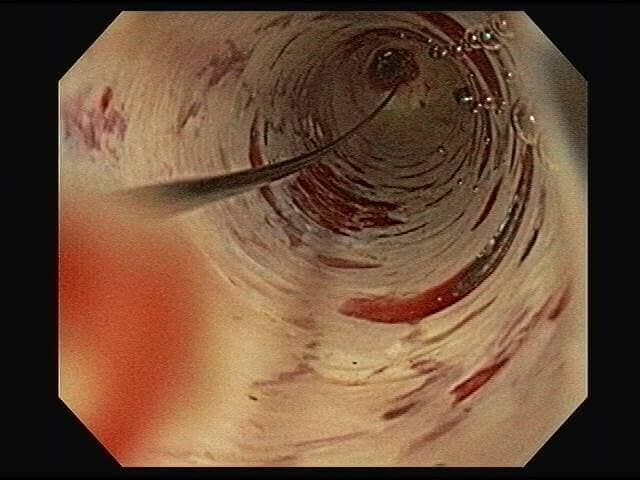

⚕ Endoscopia de alta definición

⚕ Videoendoscopia y biopsias

⚕ Videocolonoscopia